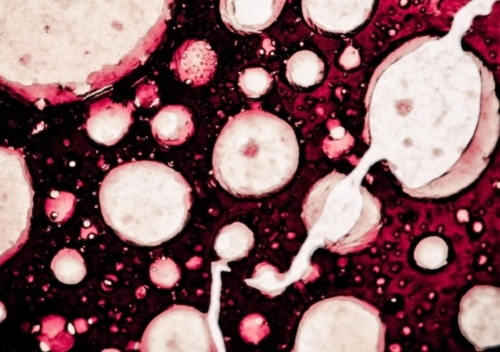

celule canceroase

Cinci alimente care distrug celulele canceroase

Cancerul poate fi tratat